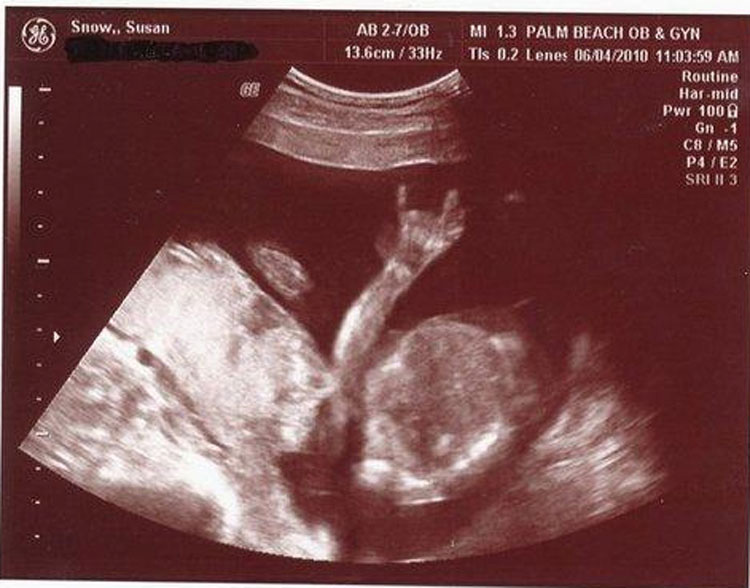

Hoy en día es algo normal que las mujeres embarazadas se hagan ecografías, o ecografías médicas, para comprobar la salud física y la evolución de su bebé antes de nacer. Una ventaja adicional de la ecografía es la posibilidad de detectar el sexo del bebé antes del nacimiento. Las propias ecografías se suelen convertir en las primeras imágenes de bebé de los niños.

Estas ecografías son a menudo compartidas con la familia, amigos e Internet, incluso aunque el bebé sea difícil de ver por ojos no entrenados. A veces esas misteriosas imágenes invitan a la pareidolia, que es nuestra tendencia a ver formas familiares en lo desconocido.

Estos son algunos ejemplos de cosas extrañas que hemos visto en imágenes de ecografías.